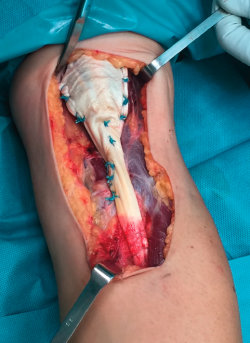

Figura 2. Imagen de la sutura distal del injerto.

La técnica de sutura del injerto de Aquiles fue la de tipo FiberLoop distalmente y anclamos el tendón mediante un botón cortical (EndoButton®, Smith & Nephew) en disposición intramedular en la tuberosidad bicipital del radio para evitar el riesgo de lesión del nervio radial. La sutura proximal fue mediante puntos de tipo Krakow intentando envolver el muñón muscular en toda su circunferencia utilizando la parte proximal del tendón de Aquiles como un abanico desplegado (Figuras 2 y 3).

Figura 3. Imagen de la sutura proximal del injerto.

Es recomendable anclar primero el injerto a nivel distal, ya que facilita encontrar la tensión adecuada de la sutura a nivel proximal, que se recomienda realizar aproximadamente a unos 45-60° de flexión del codo (Figura 4).